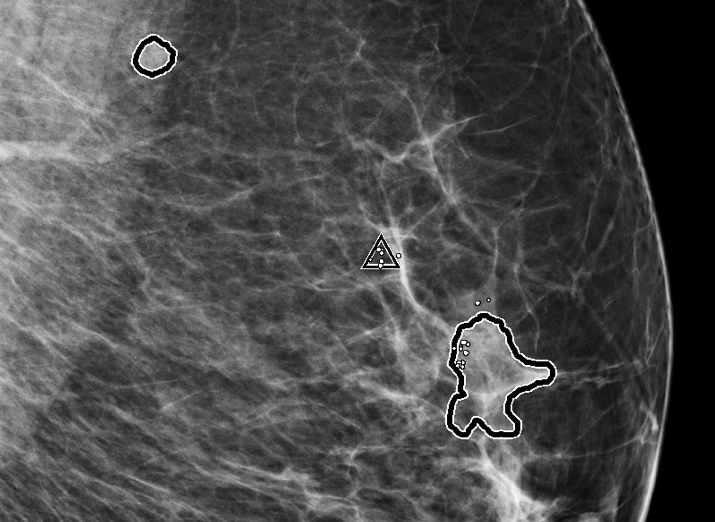

Screening & Diagnosis